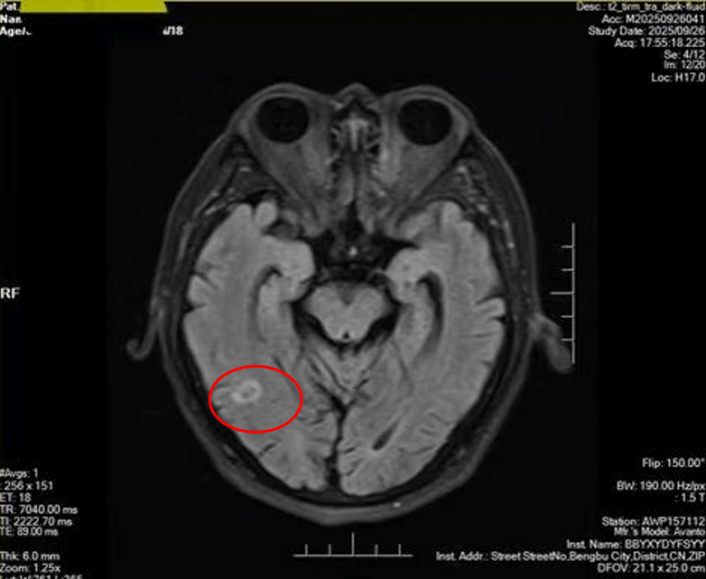

2023年10月,袁某因出现脑转移接受了脑部放疗。然而2025年10月,脑部MRI检查再次发现脑部新发转移灶。由于患者两年前已接受过全脑放疗,短期内再次传统放疗将显著增加放射性脑损伤风险。

放疗前患者脑部磁共振